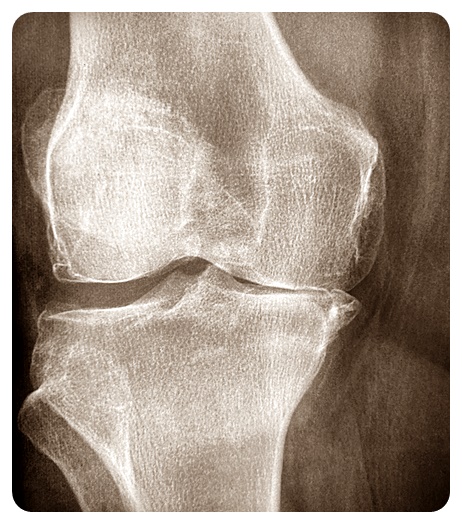

1. 골관절염

이 유형의 관절염은 일반적으로 시간이 지남에 따라 관절이 마모되어 발생합니다. 주로 노인에게 영향을 미치며 뼈 사이의 연골이 파괴되어 통증, 뻣뻣함 및 부종을 유발합니다.